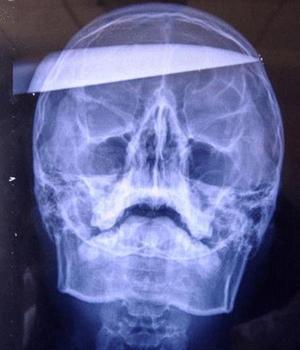

El cuchillo se clavó en la sien izquierda de Wei, sobresaliendo tan sólo el mango, y salió 1 cm por la sien derecha ."Su rostro estaba cubierto de sangre, pero aún estaba consciente," dijo el profesor Yan Shijun, subdirector del departamento de neurocirugía del hospital. Xiao Wei ya ha despertado de la cirugía, y su condición es estable.

El Dr. Yan dijo que era la primera vez en 23 años de práctica médica que había visto a un paciente permanecer consciente después de ser apuñalado en la cabeza. Los rayos X confirmaron que la cuchilla, afortunadamente no había alcanzado ninguna arteria principal. Sin embargo, el paciente puede tener complicaciones postoperatorias.